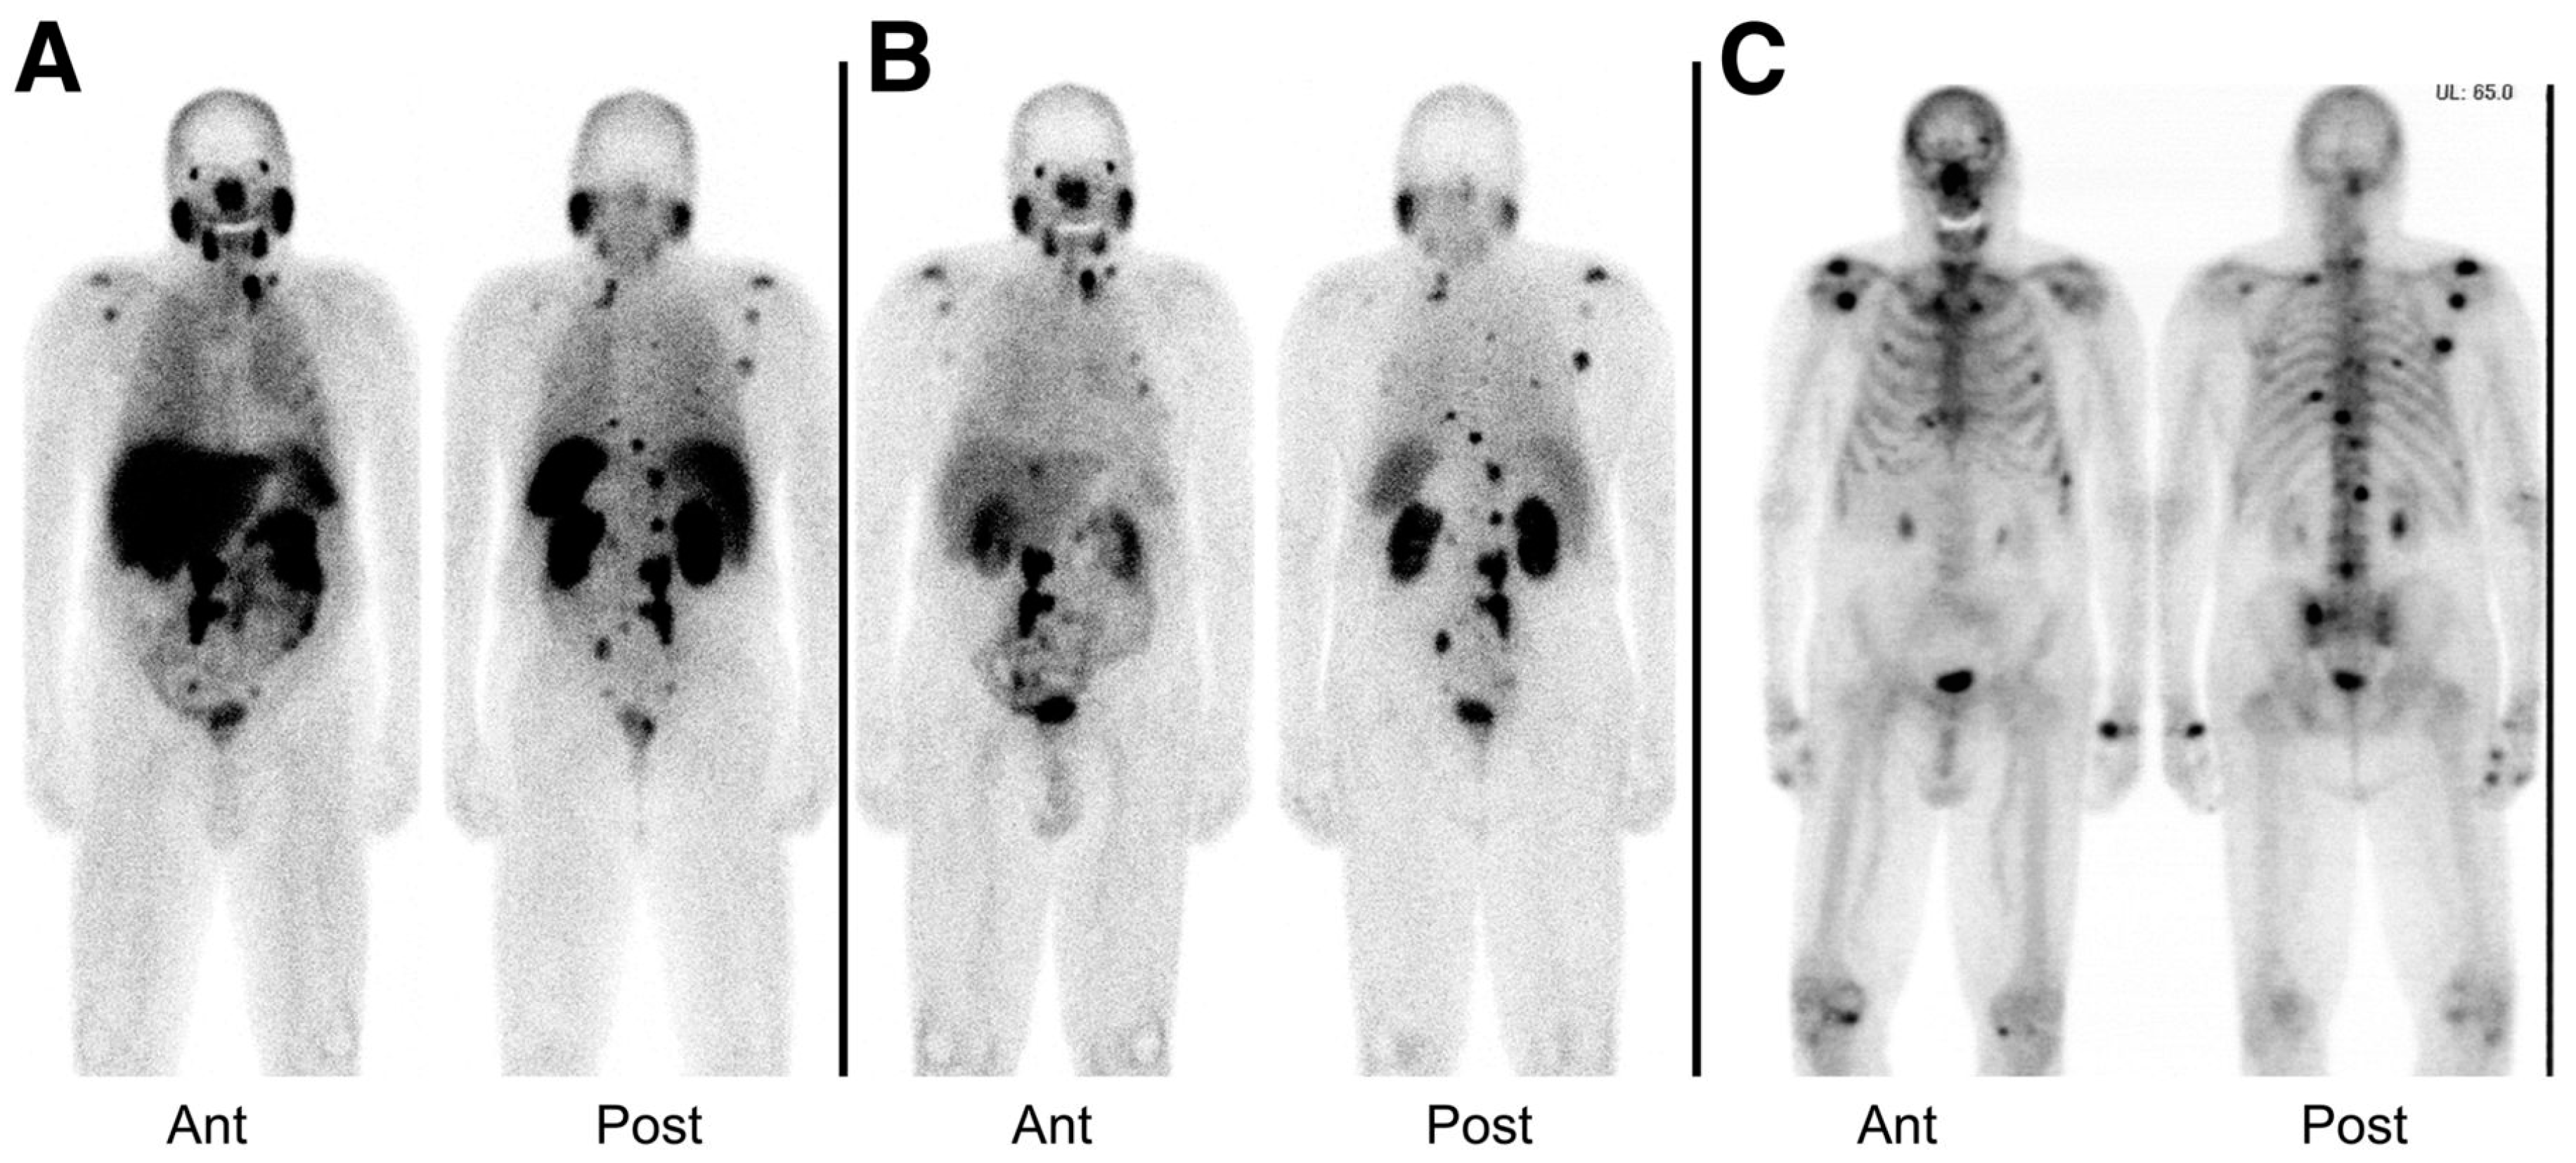

An exploratory investigational new drug application (IND) was implemented to bring the compounds MIP-1404 and MIP-1405 which been developed by the group at Molecular Insight Pharmaceuticals (MIP), and labeled with 99mTc, into the clinic. Vallabhajosula et al. [143], reported the comparison of the pharmacokinetics, biodistribution, and tumor uptake of 99mTc-MIP-1404 and 99mTc-MIP-1405 in 6 healthy men and 6 men with radiographic evidence of metastatic prostate cancer. SPECT imaging was performed between 3 and 4 h after injection of the radiotracers (Figure 18). Both radiotracers showed fast blood clearance persistent uptake in the salivary, lacrimal, and parotid glands. They localized in bone and lymph node lesions as early as 1 h. Because of the lower urinary activity of 99mTc-MIP-1404 (7%) compared to 99mTc-MIP-1405 (26%), a clear advantage for detecting prostate cancer in the gland and pelvis at early stages of the disease is indicated for this compound. 99mTc-MIP-1404 was selected for phase II studies to determine sensitivity and specificity to detect prostate cancer in high-risk patients. Furthermore, the development and optimization of a “cold” kit for the preparation of 99mTc-MIP-1404 using generator eluted pertechnetate has also been reported [144].

Figure 18.

Tumor uptake of 99mTc-MIP-1404 (A) or 99mTc-MIP-1405 (B) at 4 h in patient with metastatic prostate cancer, compared with that of standard bone scan (C). Images also show uptake of radiotracer in normal parotid and salivary glands. Ant = anterior; Post = posterior (Reprinted with permission of [143]).